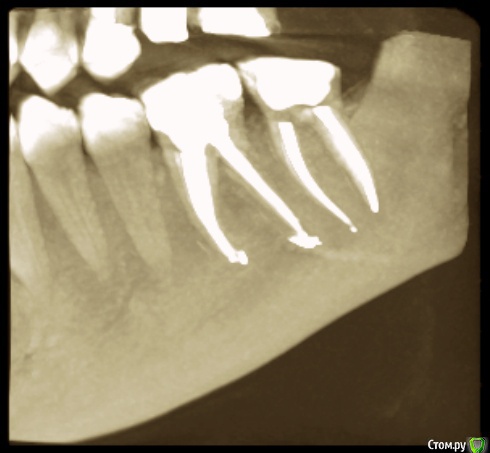

венди Опубликовано 26 января, 2017 Поделиться Опубликовано 26 января, 2017 (изменено) Добрый день! Не знаю в какой раздел будет правильно добавить, т.к. проблема смешанная. Помогите, пожалуйста! 3 месяца мучений. В прошлом году начала заниматься зубами. Был сделан панорамный снимок (прилагаю).В мае в районе отсутствующего 26 был установлен имплант с одновременным открытым синус-лифтингом. Послеоперационный период протекал более-менее нормально. Меня отпустили на пол года. И я стала заниматься остальными зубами. Лечили кариес справа, был удален 46 (резорбация мед. стенки медиального корня с перфорацией). К осени добрались до левой нижней стороны. 26.09. - был залечен кариес в 36 зубе. После этого зуб стал стрелять током при накусывании. Врач решила ещё понаблюдать.19.10. - 37 зуб с гранулемой был распломбирован, врач прошла каналы, заложила кальций. Через 6 дней ещё раз все прочистили, запломбировали каналы полностью, поставили временную пломбу и сказали, что можно протезироваться. Вроде зуб после лечения не беспокоил.01.11. - я пошла на осмотр к хирургу по поводу удаленного 46. Хирург решил раскрыть имплант, т.к. уже время подошло. Сказал всё хорошо прижилось и поставил формирователь десны. С этого дня моя жизнь разделилась на до и после.. Стала болеть вся область вокруг импланта, появилось ощущение мешающего валика под щекой, формирователь утонул в десне, отечность в этой области была. Обобщу и скажу, что после этого формирователь перекручивался еще 3 раза, внутри все промывалось, я принимала антибиотики. Острые ощущения немного ушли, но дискомфорт мешающий нормально жить оставался. По снимку - все отлично, имплант интегрирован (прилагаю). Одновременно с этими манипуляциями с имплантом 36 зуб стал не только бить током, а до него уже нельзя было дотронуться. 18.11 - вскрыли, депульпировали, заложили кальций и через неделю закрыли все постоянной пломбой (снимок прилагаю). Всё это время, впрочем как и сейчас вся левая сторона была охвачена ужасными ощущениями. Распирание, нытье, давящая боль, дискомфорт и днем и ночью. Стала плохо спать. Перед Новым Годом хирург принял решение выкрутить формирователь и посмотреть за динамикой. Мне показалось, что стало немного легче, особенно что касается ощущение валика под щекой. НО все равно с левой стороны мне что-то болит. От области импланта ли это идет или от 36-37 - я не знаю, не могу точно дифференцировать.... т.к. ковырялись везде одновременно и у меня уже все спутано... Никто не может понять, что со мной, т.к. по снимкам и 3Д все отлично. На прошлой неделе придя в очередной раз в клинику - по панорамному снимку и моим жалобам на боли поставили диагноз "дисфункция ВНЧ, артроз ВНЧС слева". При этом я спокойно открываю рот без болей, щелчков и хруста, при жевании тоже ничего не болит. Назначили физио и Аэртал - принимаю больше недели вообще все без изменений... аэртал даже не обезбаливает особо. На данный момент я ощущаю постоянный тупой ноющий тянущий дискомфорт слева. Чувство распирания. Поднимается иногда температура 37-37,1. Плохо сплю, нервничаю, т.к. очень снизилось качество жизни. Помогите, пожалуйста, разобраться. На что бить, если по снимками как бы все хорошо?! Имплант, 36, 37, сустав?? Все началось с раскрытия имланта. До этого я жила обычной жизнью. Есть 3Д декабрьские. Если кто-то захочет посмотреть я добавлю. Спасибо! Изменено 26 января, 2017 пользователем венди Ссылка на комментарий

венди Опубликовано 27 января, 2017 Автор Поделиться Опубликовано 27 января, 2017 (изменено) Сегодня была у невролога. Он сказал, что если стоматологи не находят причин, то нужно начинать прием легких успокаивающих средств и смотреть за динамикой.Неужели эту боль придумывает голова? У меня уже сил нету это терпеть. До лечения ведь вообще ничего не болело. Тянет-распирает-ноет-давит преимущественно снизу в районе 36 и 37 зуба. Подскажите, пожалуйста, может ли 37 зуб с перелеченной гранулемой так болеть? Может нужно еще раз вскрыть?Или это 36 где был пульпит и где утолщен корень как бы? Не хочется лезть в зубы без необходимости, но и жить с таким дискомфортом очень тяжело. Изменено 27 января, 2017 пользователем венди Ссылка на комментарий